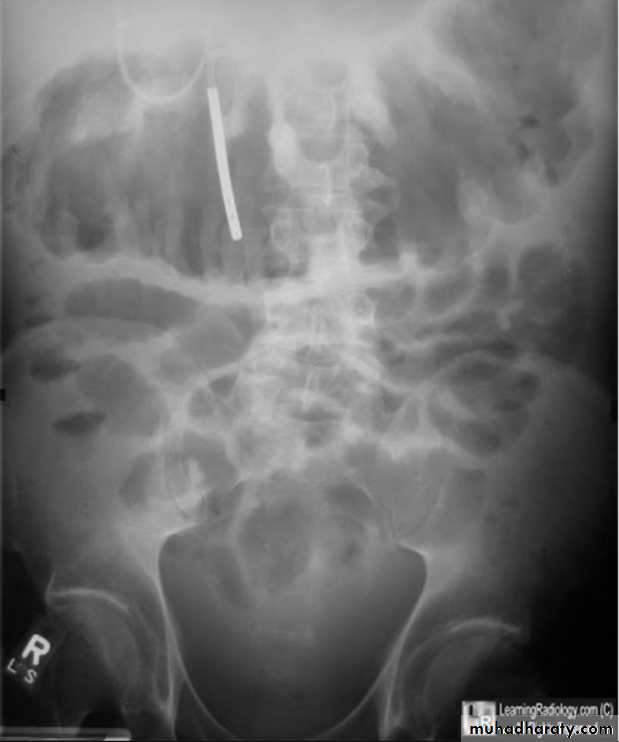

Small bowel enema

Tube in 4th part of duodenum

Better distension and delineation of small bowelBarium enema

Feathery appearance

Valvulae conniventes